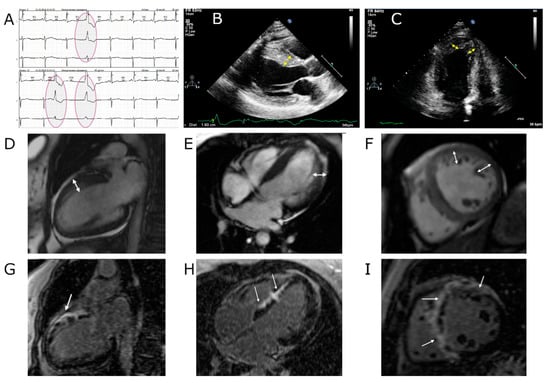

| III-2 | 44 y.o., noncompaction cardiomyopathy, heart failure, arrhythmia |